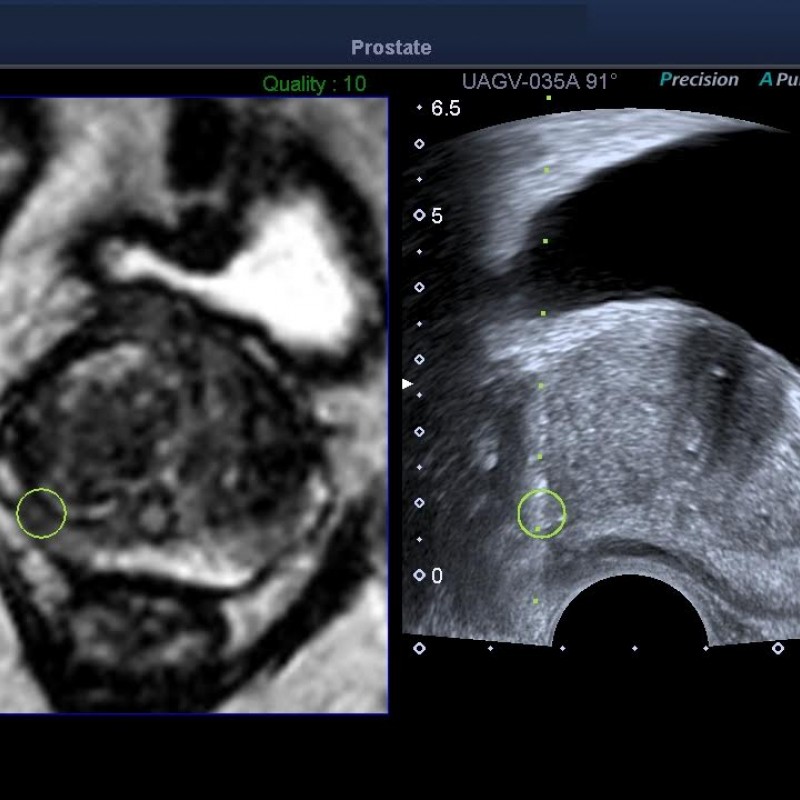

Clínica Molinón, centro pionero Smart Fusion de Toshiba.

La biopsia guiada por fusión con tecnología Toshiba llega a la medicina privada asturiana.

Es un placer anunciar que Clínica Molinón vuelve a ser noticia a nivel local y nacional por ser centro de medicina privada pionero en innovación médica y tecnológica al emplear la tecnología Smart Fusion de Toshiba…